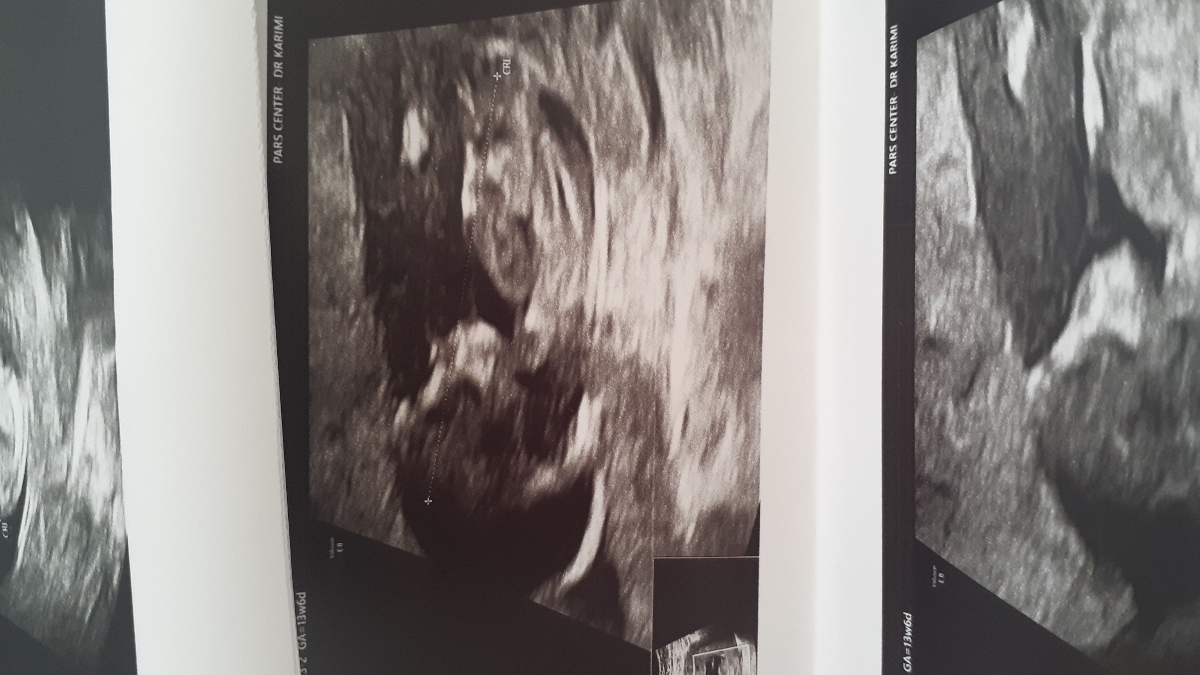

عکس سونوت بفرس

1

این دختره

این پسره